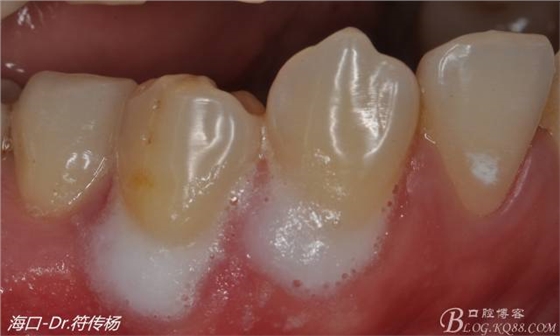

從病例圖片我們可以看到44牙頰側(cè)牙齦出現(xiàn)明顯萎縮

術(shù)前評(píng)估:退縮的齦緣在MGJ冠方 近遠(yuǎn)中牙槽嵴頂高度正常屬于Miller -Ι類牙齦退縮 所有術(shù)后可以完全覆蓋